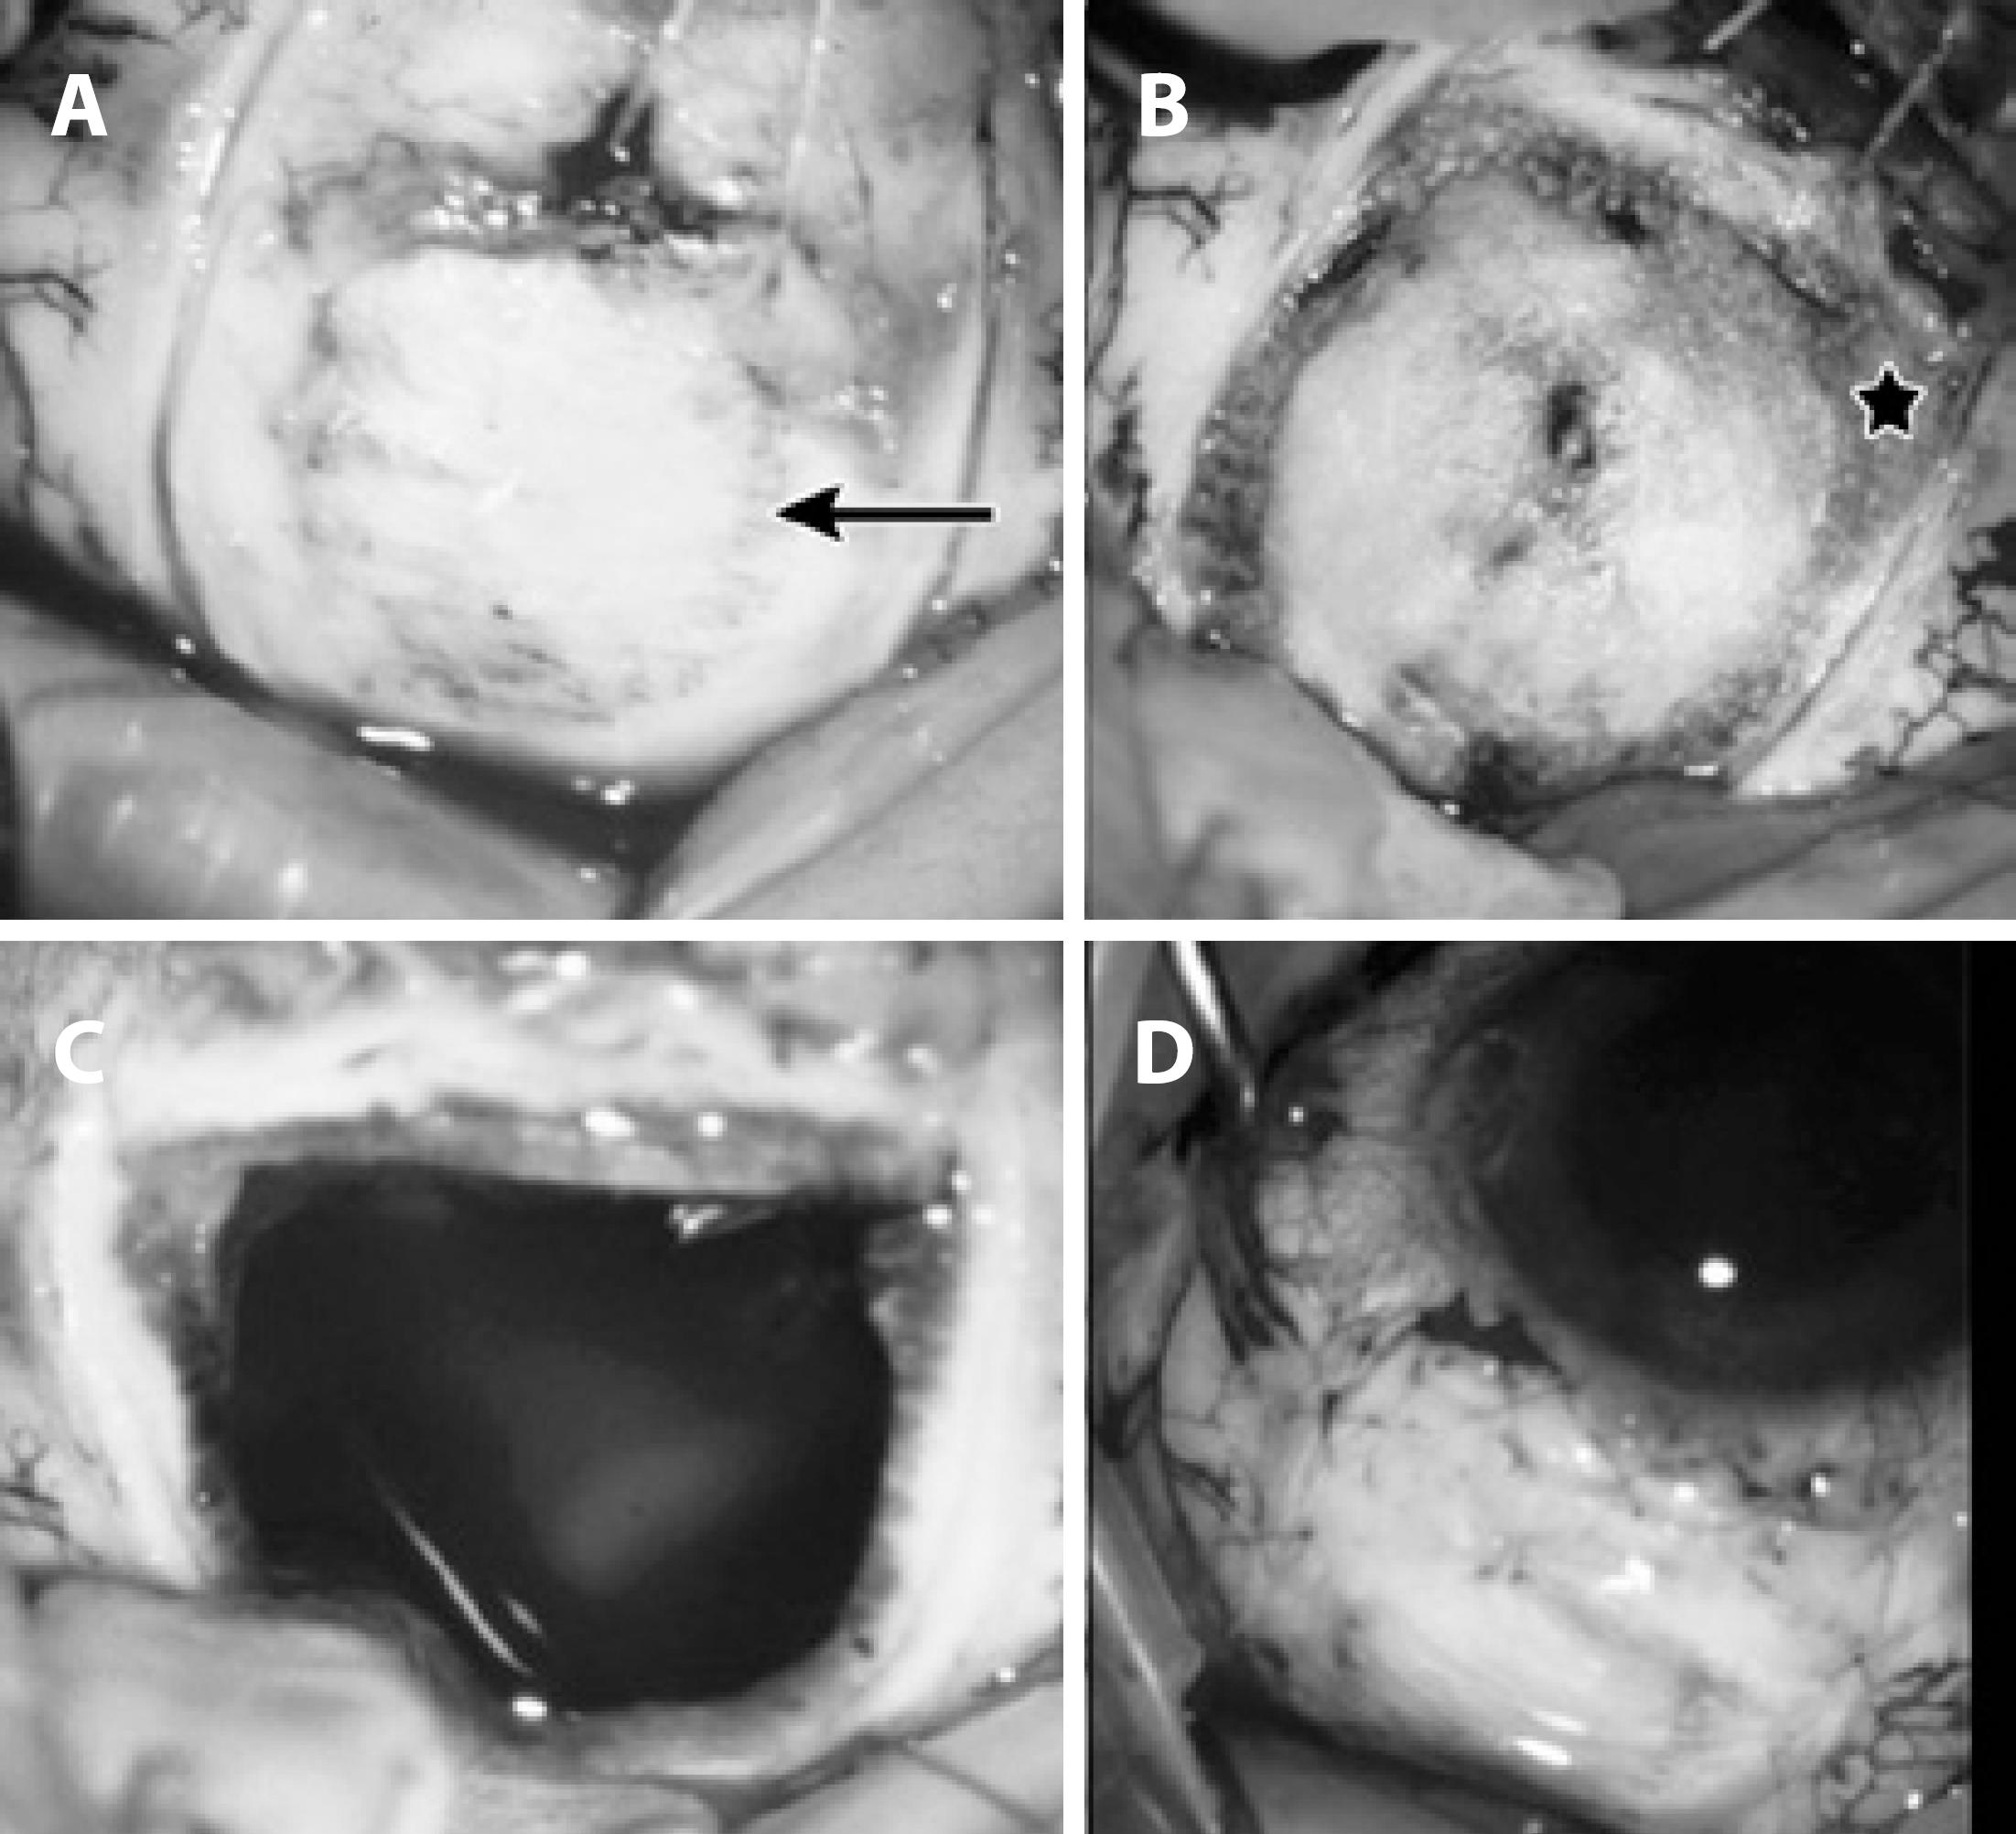

Scleral wall delamination was performed in two-thirds of the scleral thickness and respecting a safety margin of 2–3 mm of the tumor boundaries that were previously demarcated (Figure 1).

Figure 1 A) Eyeball showing sclera and inferior rectus muscle removed from the insertion. After transillumination (arrow), uveal tumor boundaries were demarcated with scleral tono-pen, and delamination was performed in two-thirds of the scleral wall respecting the tumor safety margin of 2-3 mm. B) Eyeball showing delaminated scleral flap and diathermy marks (star) at the edge of the delamination over the remaining scleral bed. C) Scleral wall was removed en bloc with the tumor and apparent vitreous humor. D) Scleral flap was sutured with nylon 9/0.

Subsequently, diathermy of the scleral bed was performed at the junction between the delaminated and non-delaminated sclera to prevent bleeding during incision (Figure 1B). A pars plana vitrectomy infusion line was placed away from the area to be resected. Subsequently, an incision in the delaminated sclera, choroid, and retina was performed for en bloc resection of the tumor (Figure 1C), and the remaining scleral flap was sutured with nylon 9/0 (Figure 1D). Finally, vitrectomy was performed to remove clots and vitreous bands attached to the incision, fluid-gas exchange, and air injection into the vitreous cavity.